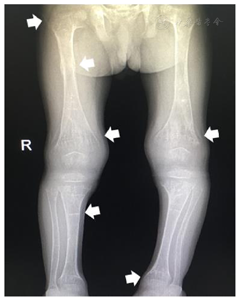

入院体格检查:身高85.5 cm(<-3SD),体重11.75 kg(<-3SD),神志清,乏力,非匀称型身材矮小,皮下脂肪菲薄。方颅,前额宽大突出。双眼轻微内斜视,视力正常,眼球运动正常。双侧耳位偏低,耳廓正常。牙列不齐,伴龋齿,脸颊饱满。肋骨外翻,7~10肋可见肋骨串珠,心肺查体未见明显异常,腹部膨隆。四肢短小,可见手镯征、脚镯征,双膝内翻,膝间距8 cm,四肢肌力Ⅳ级,肌张力减低(图1)。

影像学检查:X线片可见四肢长骨骨质稀疏,干骺端边缘模糊不规则,呈杯口样变形,先期钙化带呈毛刷状改变,符合佝偻病(活动期)改变(图2)。头颅MRI示双侧侧脑室前角及后角旁白质异常信号,双侧侧脑室前角旁分别一囊状信号影,边界清,左右侧大小约8.2 mm×3.5 mm、8.7 mm×6.5 mm。